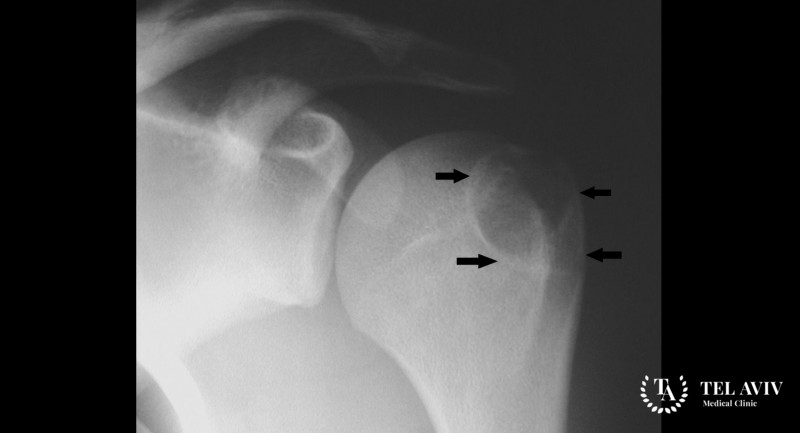

- Основным способом идентифицировать новообразование является рентгенография, на которой видно локализацию нароста и его контуры.